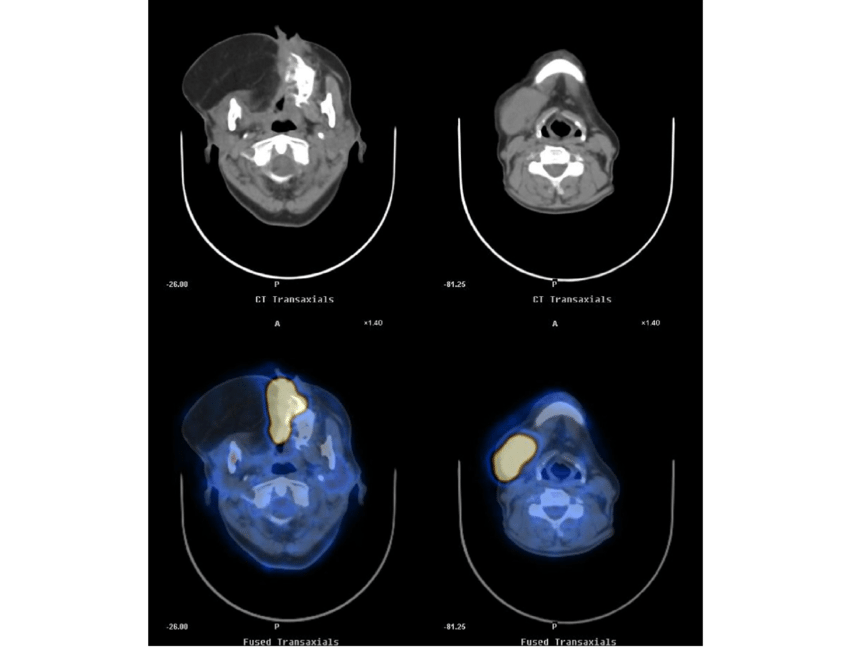

• PET or PET-CT scan is a type of positron emission tomography (PET). A PET scan is frequently paired with a CT scan, which is referred to as a PET-CT scan. However, your doctor may refer to this technique simply as a PET scan. The patient is given a small amount of radioactive sugar material to inject into his or her body. The cells that use the most energy absorb this sugar molecule. Cancer absorbs more of the radioactive substance since it uses energy actively. The material is then detected by a scanner, which produces images of the inside of the body.

• CT (computed tomography) is a type of imaging that uses a (CT or CAT scan). A CT scan uses X-rays captured from various angles to create images of the inside of the body. These images are combined by a computer into a detailed, three-dimensional image that reveals any anomalies or malignancies. A CT scan can be performed to determine the size of the tumour. Before the scan, a specific dye called a contrast medium is sometimes used to improve image detail. This dye can be injected into a patient's vein or given to them in the form of a tablet or drink.

Imaging tests are performed. Before surgery, imaging procedures such as magnetic resonance imaging (MRI) or computed tomography (CT) scan can assist doctors in seeing the size and position of the tumour. If the tumour has migrated to other parts of the body, a positron emission tomography (PET) scan may be employed.